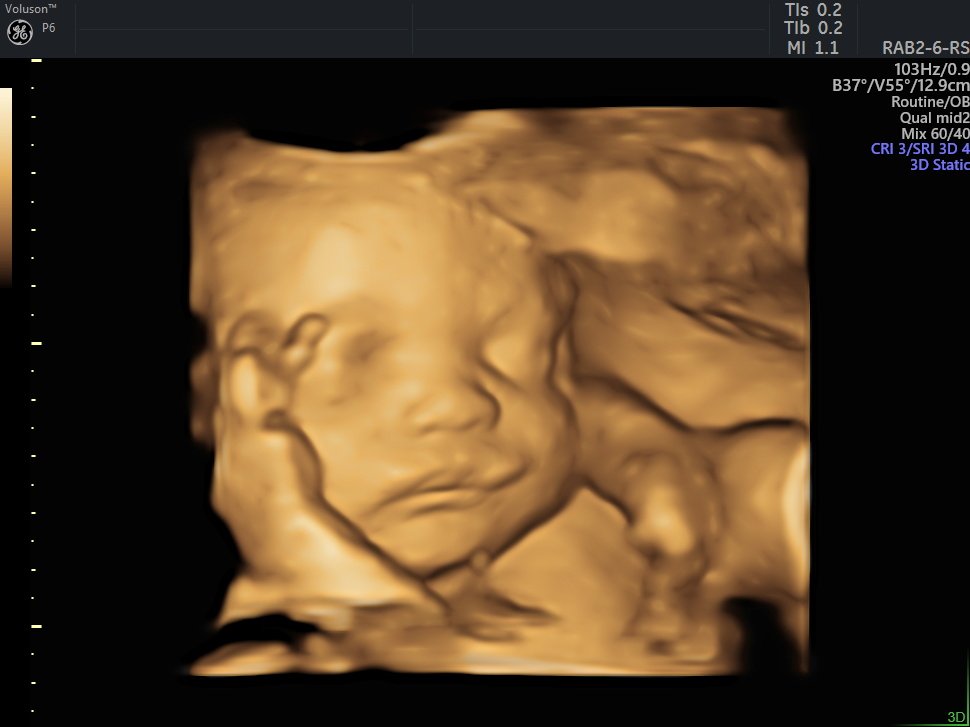

4 Boyutlu (Renkli) Ultrason ve Doppler Ultrasonografi

4 D Ultrasonografi